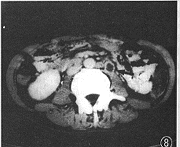

图8 同图5病例,腹膜后淋巴结肿大,有环形强化(↑)

3. 胸部以外的影像表现:颈部淋巴结肿大2例,合并锁骨上淋巴结肿大(图7)。淋巴结融合肿块最大3.5 cm× 5.5 cm。腹膜后淋巴结肿大1例,腹部CT见后腹膜有多个肿大淋巴结,最大直径1.8 cm,增强扫描淋巴结边缘有环形强化(图8)。